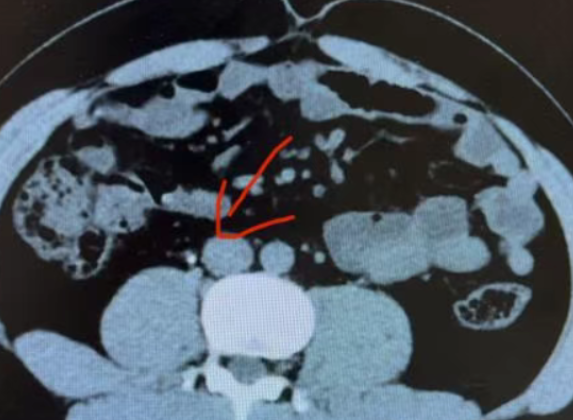

从事泌尿外科、普外科微创工作20余年,从事泌尿外科、普外科微创工作20余年,主要从事泌尿结石、胆结石、前列腺、肾脏等外科常见病的诊断及腹腔镜、输尿管镜、肾镜、前列腺电切的微创治疗:双镜联合取石术、胆总管切开一期缝合术、腹腔镜阑尾切除术、腹腔镜疝修补术等。本院外科专家简介胡育琴外科副主任医师三峡大学客座教授原北京总后医院结石病研究中心成员毕业于湖北中医药大学医疗系,深耕结石病诊疗领域40余载,对复杂性结石疑难病例有独到见解,秉持“精准施治”的诊疗理念。

为每位结石患者制定创伤最小、康复最快的个性化治疗方案。在微创取石领域建树颇丰,累计完成各类结石手术两万余例,在广大结石患者中享有盛誉。具有深厚的学术造诣,先后在国家核心刊物发表专业论文40余篇,多次获科研成果奖等殊荣。